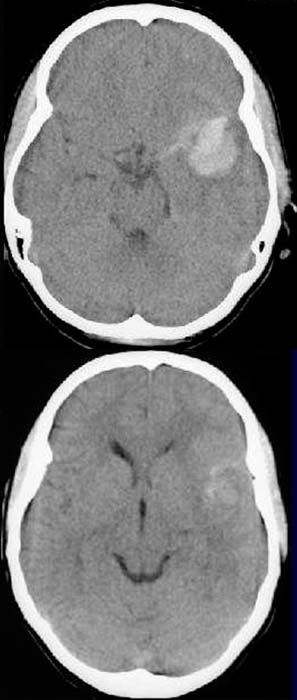

CCT nativ (ohne Kontrastmittel).

Hyperdense

Darstellung der Sulci

links temporal. Hyperdense Raumforderung in der sylvischen

Furche links. Hyperdense intracerebrale

Raumforderung links. Asymmetrische

Darstellung des Temporallappens links. Kompression des

linken Seitenventrikels.

V.a.

rupturiertes A. cerebri media Aneurysma links mit Subarachnoidalblutung

und intracerebraler Blutung links temporal mit

raumfordernder Wirkung.